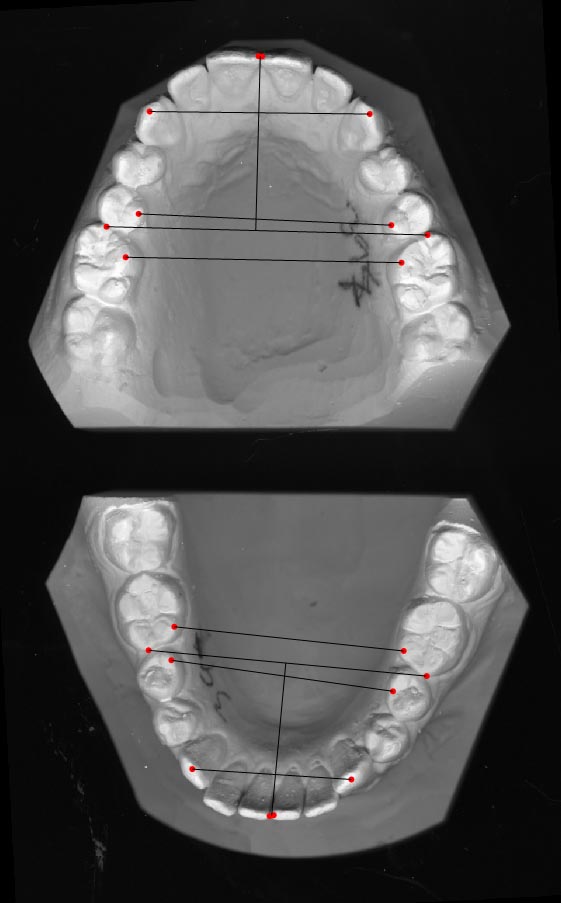

Study models – Model analyses

There are a handful of analyses suitable for study models included in Facad, namely

Arch form, Bolton, Morrees, and Schwarz-Korkhaus.